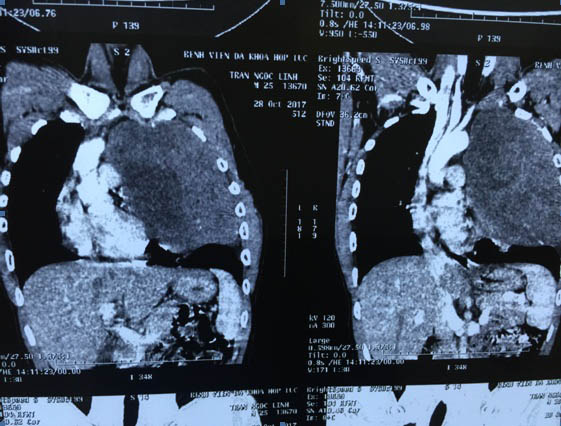

Sau khi làm các thủ tục chụp chiếu, xét nghiệm bệnh nhân được chẩn đoán u thần kinh trung thất trên trái. Khối u chiếm toàn bộ khoang lồng ngực trái, kéo dài từ nền cổ tới gần sát cơ hoành, đè đẩy tim và các mạch máu lớn, làm xẹp nhĩ trái.

Cực trên khối u chèn ép vào bó mạch thần kinh cánh tay, cực dưới đè đẩy xẹp gần như toàn bộ phổi trái. Kết quả sinh thiết kim chẩn đoán giải phẫu bệnh kết luận u xơ thần kinh lành tính.